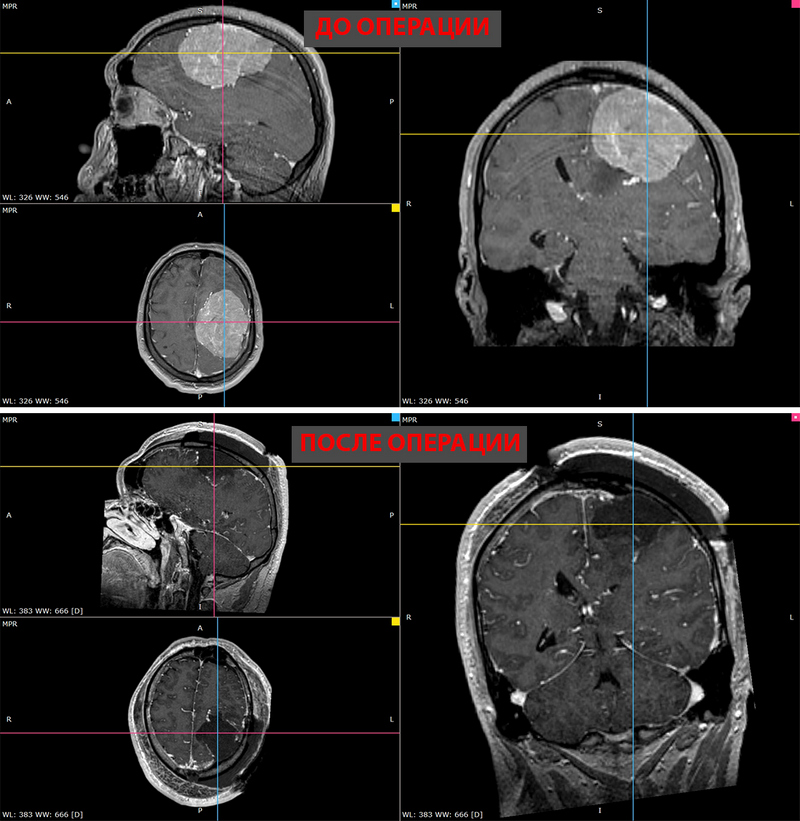

Выявить причину помогло МРТ-исследование: в левом полушарии обнаружили менингиому больше 8 см в диаметре. Опухоль сдавливала центры, ответственные за речь и движения правых конечностей.

«Для столь гигантского объема опухоли это не так уж много, - делится доктор Чернов. - Важно было удалить ее полностью по краю области, где она росла, только это могло обеспечить хороший результат. И это удалось. Контрольное МРТ-исследование показало: опухоли нет, как и кровоизлияний, и ишемических нарушений.